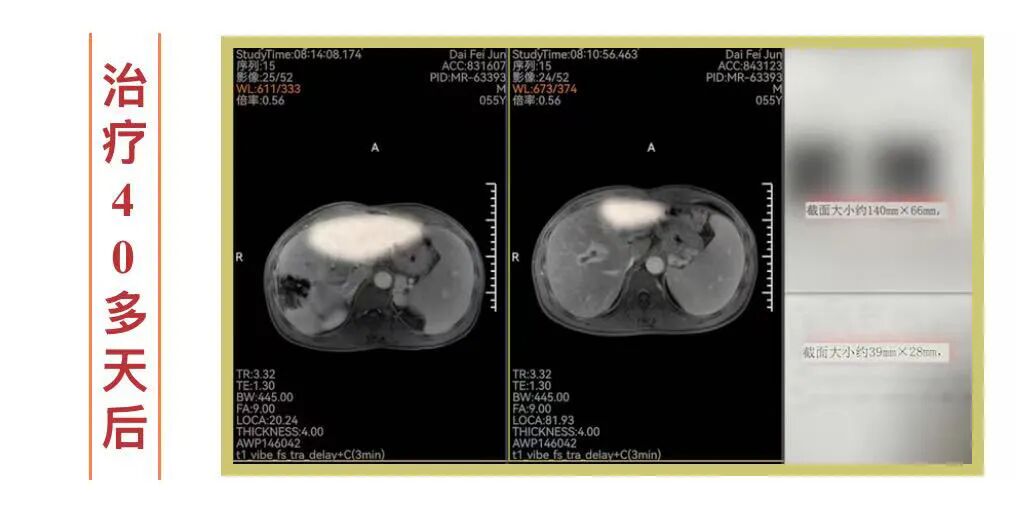

▍“靶向+免疫+中药”,仅用40多天,肝癌从14cm“缩”成3.9cm!

十几年来,宁波人戴先生(化名)一直与肝癌搏斗。2023年,2次被切除的癌肿再次卷土重来时,他几乎被宣判“死刑”——多处种植性转移,癌肿越长越大,最大的甚至达到14cm,并出现了比肿瘤更凶险的“癌栓”……

身体每况愈下的戴先生不甘坐以待毙,在2024年秋天找到了钟伟主任,决定尝试中西医结合的新路径。在“靶向+免疫+中药”的治疗方案下,奇迹很快出现:仅40多天,那枚14cm的肿瘤显著缩小至3.9cm;8个月后的今天,肿瘤仅剩3cm,其余小病灶已消失,致命的癌栓也已钙化脱落!